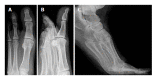

Hallux rigidus describes the osteoarthritis of the first metatarsophalangeal joint. It was first mentioned in 1887. Since then a multitude of terms have been introduced referring to the same disease. The main complaints are pain especially during movement and a limited range of motion. Radiographically the typical signs of osteoarthritis can be observed starting at the dorsal portion of the joint. Numerous classifications make the comparison of the different studies difficult. If non-operative treatment fails to resolve the symptoms operative treatment is indicated. The most studied procedure with reproducible results is the arthrodesis. Nevertheless, many patients refuse this treatment option, favouring a procedure preserving motion. Different motion preserving and joint sacrificing operations such as arthroplasty are available. In this review we focus on motion and joint preserving procedures. Numerous joint preserving osteotomies have been described. Most of them try to relocate the viable plantar cartilage more dorsally, to decompress the joint and to increase dorsiflexion of the first metatarsal bone. Multiple studies are available investigating these procedures. Most of them suffer from low quality, short follow up and small patient numbers. Consequently the grade of recommendation is low. Nonetheless, joint preserving procedures are appealing because if they fail to relief the symptoms an arthrodesis or arthroplasty can still be performed thereafter.